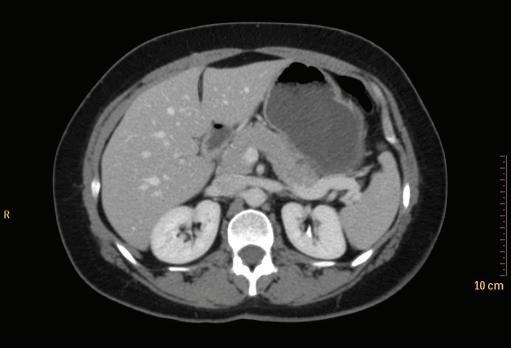

Axial CT images are presented as if the viewer is standing at the foot of the patient’s bed; the patient’s right is to viewer’s left; the anterior aspect of the patient is toward the top of the image (Fig. 1-17). Coronal images are viewed the same way that the majority of radiographs are viewed; the images are oriented as though the patient is looking at you (Fig. 1-18).

FIGURE 1-17 Axial CT of the abdomen.